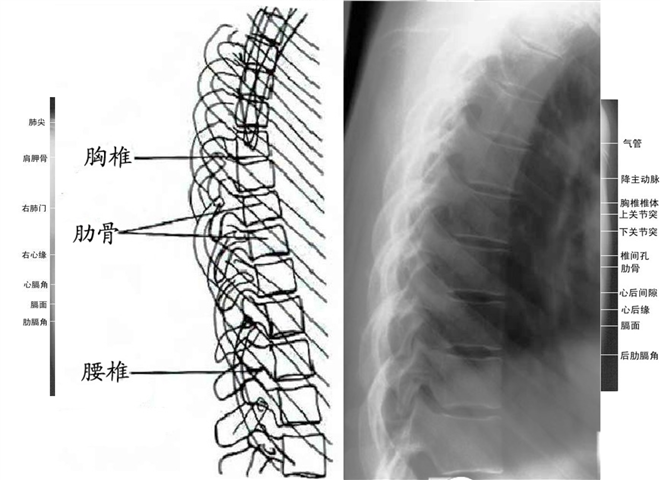

正常腰椎x光片图

正常腰椎x光片图,腰椎x光片 正常

腰椎特性,结构分解,附上诊断方法及x光片检查

正常脊柱图片x片

正常全脊柱x光片图片

脊柱X光片

正常腰椎x光片图 图解

腰椎x光片讲解